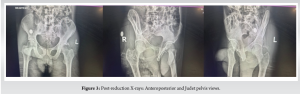

A 46-year-old male initially presented to a primary care facility after being involved in a pedestrian-vehicle accident and sustaining bilateral hip injuries. The primary care facility ordered X-rays and attempted to reduce the bilateral hip injuries he suffered but was unsuccessful. He was then referred to a tertiary-level facility. Upon arrival, he was evaluated by both the trauma surgery team and the on-call orthopedic team. Although intoxicated at the time, he complained of bilateral hip pain only and an inability to bear weight. He gave no history regarding any head, chest, or abdominal injuries. He confessed to being inebriated. He denied any previous medical or surgical history. He did not have any allergies, nor was he on any medication. He was at the time unemployed. He was evaluated according to the advanced trauma life support principles on clinical examination. He was kept in headblocks as his cervical spine could not be clinically cleared, as he had distracting injuries, and he was intoxicated at the time. His airway was otherwise self-maintained. He had good air entry bilaterally, which was clear on the auscultation of his chest. All his pulses were present, he was hemodynamically stable, and there were no signs of bleeding from anywhere. His Glasgow coma scale was 14/15 due to his intoxication; there were no overt focal neurological sequelae identified. He did not have any open wounds on exposure. His musculoskeletal examination revealed his left hip flexed, adducted, and internally rotated. He had tenderness in the groin and the lateral aspect of his hip. Range of motion at the hip was deferred due to the pain. His dorsalis pedis and posterior tibialis pulses were palpable and comparable to the contralateral side. He was able to dorsiflex and plantarflex his ankle and toes. His right hip was extended and externally rotated. He was tender in the groin, and there was also a fullness and a palpable firmness in the right groin. Range of motion was also deferred in that hip secondary to pain. However, he could still dorsiflex and plantarflex his toes and right ankle, and his dorsalis pedis and posterior tibialis pulses were present. The plain radiographs (Fig. 1) that were done showed that he had suffered a left posterior hip fracture-dislocation and a right anterior hip fracture-dislocation. The left hip was classified as a Thompson and Epstein type 2, and the right hip was classified as a Thompson and Epstein type 1C. He was then counseled and given conscious sedation using a combination of ketamine and propofol under continuous monitoring of his vitals in the resuscitation bay. We reduced the left hip using the Captain Morgan technique and the right hip using the Allis leg extension technique. Both hips were stable post-reduction, and the patient’s neurological function remained intact. The reductions were carried out within 24 h from the time of injury. Bilateral lower limb in-line skin traction (Fig. 2) was applied with 4 kg weights. Post-reduction plain radiographs (Fig. 3) of the pelvis (anterior–posterior and Judet views) confirmed that the hips were reduced. There was a posterior acetabular wall fracture on the left and a small anterior-superior acetabular wall fracture on the right.